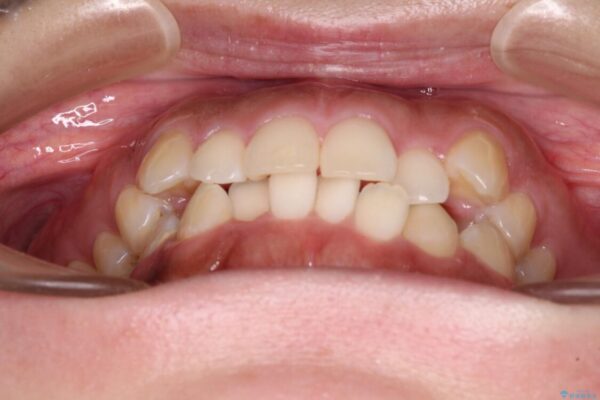

治療後

• 【モニター】カリエール・ディスタライザーを併用した八重歯のインビザライン矯正 治療後画像

カリエールディスタライザーを併用したことで、すっきりとした口元になり、上下の正中を合わせることができました。